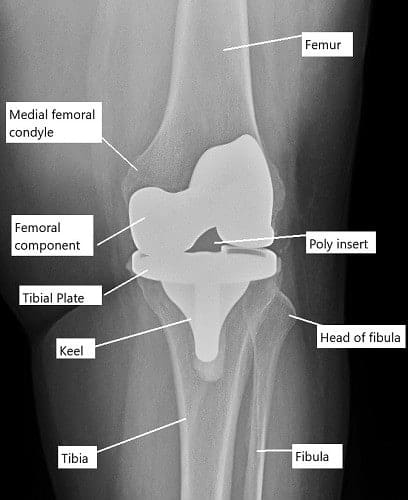

El diagnóstico comienza con una historia clínica detallada y un examen. El médico revisa el movimiento de las articulaciones, la fuerza y la estabilidad. Las radiografías muestran aflojamiento, alineación y pérdida ósea. Las tomografías computarizadas ayudan a evaluar la posición de los componentes. La resonancia magnética puede mostrar daño óseo. Una gammagrafía ósea puede detectar infección o aflojamiento. Las aspiraciones articulares y los análisis de sangre buscan signos de infección.

Las imágenes anteriores muestran componentes femorales y tibiales modulares. Los componentes modulares permiten al cirujano realizar ajustes intraoperatorios para lograr una mayor estabilidad. Existen disposiciones para fijar tallos a los componentes, así como añadir aumentos óseos para compensar la pérdida ósea sufrida durante la cirugía.

Los insertos de polietileno restringidos en las imágenes anteriores utilizan un poste tibial alto y ancho para proporcionar estabilidad lateral y rotativa. Estos insertos se utilizan habitualmente con componentes femorales y tibiales con tallos. Los tallos disipan el esfuerzo adicional que surge del constructo restringido.